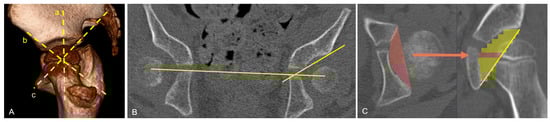

Individualized 3D Planning for Hip Reconstruction in Cerebral Palsy: Study Protocol

by Britta K. Krautwurst, Thomas Dreher, Franziska L. Hatt, Bastian Sigrist, Tobias Götschi and Domenic Grisch

Background: In children with cerebral palsy, bony acetabular deficiencies are common and may be associated with progressive hip subluxation, abnormal joint loading, and ultimately hip dislocation. Hip reconstruction surgery is typically performed to prevent dislocation, and this includes acetabular reshaping using acetabuloplasty. The [...] Read more.

Background: In children with cerebral palsy, bony acetabular deficiencies are common and may be associated with progressive hip subluxation, abnormal joint loading, and ultimately hip dislocation. Hip reconstruction surgery is typically performed to prevent dislocation, and this includes acetabular reshaping using acetabuloplasty. The location of acetabular deficiency may vary among individuals; however, only radiographs are used for planning and intraoperative correction in many centers. Precise reconstruction and preop planning are necessary for the accurate correction of acetabular coverage. This study compares conventional hip reconstruction with a 3D-guided technique using individual preop 3D planning and 3D-printed guides during surgery to determine which method allows for a more accurate correction. We hypothesize that the patient-specific 3D planning leads to more precise anatomical correction of acetabular coverage compared to conventional freehand osteotomy. Methods: This study was registered in the German Clinical Trial Register (DRKS-ID: DRKS00031356) on 14 July 2023. In a randomized controlled trial, various imaging-based parameters were used to assess the bony anatomy preoperatively and postoperatively. Preoperative and 6-week postoperative computed tomography (CT) scans are part of routine clinical care. Additionally, an immediate postoperative CT scan was performed. One hip was operated on using individualized 3D preoperative planning, while the other hip was corrected using a conventional surgical approach. A standardized subtrochanteric osteotomy was performed for the varisation, derotation, and shortening of the proximal femur. This osteotomy was followed by acetabuloplasty under fluoroscopic control. For the 3D-planned operation, patient-specific cutting and repositioning guides were produced based on preoperative CT imaging. Patients with bilateral cerebral palsy (GMFCS levels I–V), aged 4–18 years, with an open triradiate growth plate and a migration index ≥ 40% in at least one hip were included. In a preliminary retrospective part, this project reproduces the existing three-dimensional acetabular index (3-DAI) and compares it with established radiographic methods to determine the utility and reliability of a reconstructed 3D CT measurement technique. A further component of the retrospective part is the creation of an age-adjusted database of typically developed hips and the development of a 3D head coverage index (3D-HCI) as a new 3D parameter to express acetabular coverage; therefore, it will be used as a secondary parameter and correlated to the 3DAI in the prospective part. Conclusions: Improved precision may have meaningful clinical implications for long-term joint congruency, load distribution, pain, and mobility outcomes. Full article

Show Figures

Figure 1